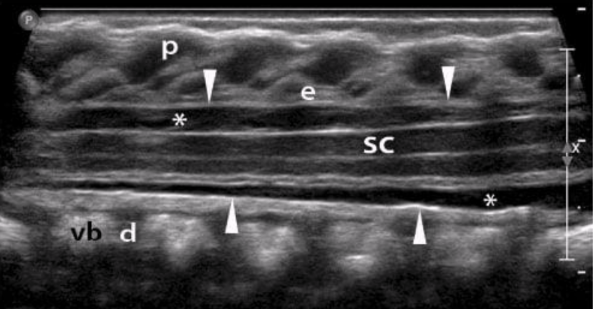

vb

vertebral bodies

d

intervertebral disks

p

spinous processes

arrowheads

arachnoid/dural layer

e

epidural space

*

subarachnoid space w/ CSF

sc

hypoechoic spinal cord